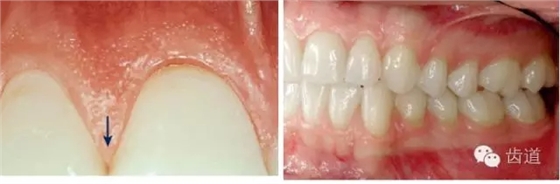

1、口腔衛(wèi)生狀況及局部刺激物(牙菌斑、牙石,不良修復體)

牙石及不良修復體

2、牙齦

(顏色、形狀、質地、退縮、BOP、PD、附著齦)